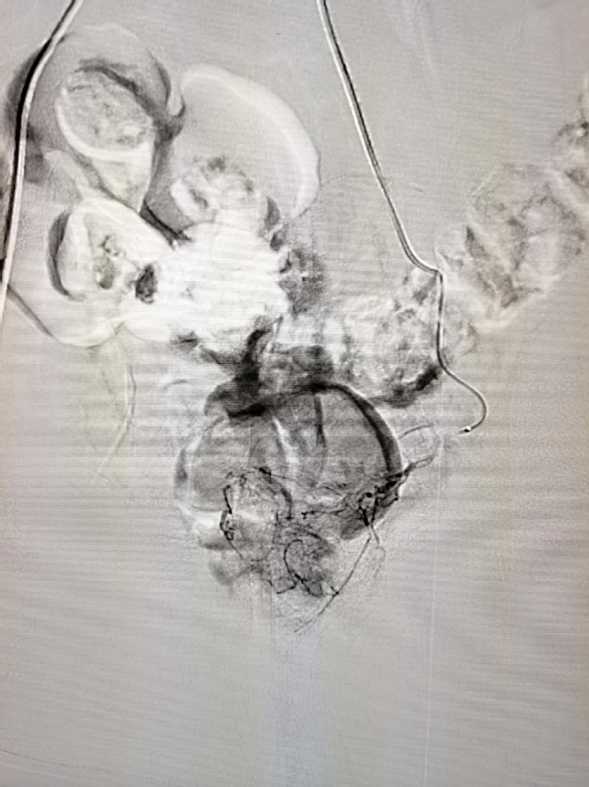

术中左侧前列腺动脉造影结果